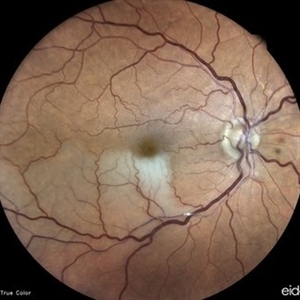

Fundus photograph of a 43-year-old myopic man (left eye) Axial length: 29.32 mm

Photographer: Bruno DECAY, MD

Imaging device: iCARE EIDON confocal fundus imaging system (Ultra-Widefield Module)

Condition/keywords: Bilateral, High myopia, Pigmented Paravenous Retinochoroidal Atrophy